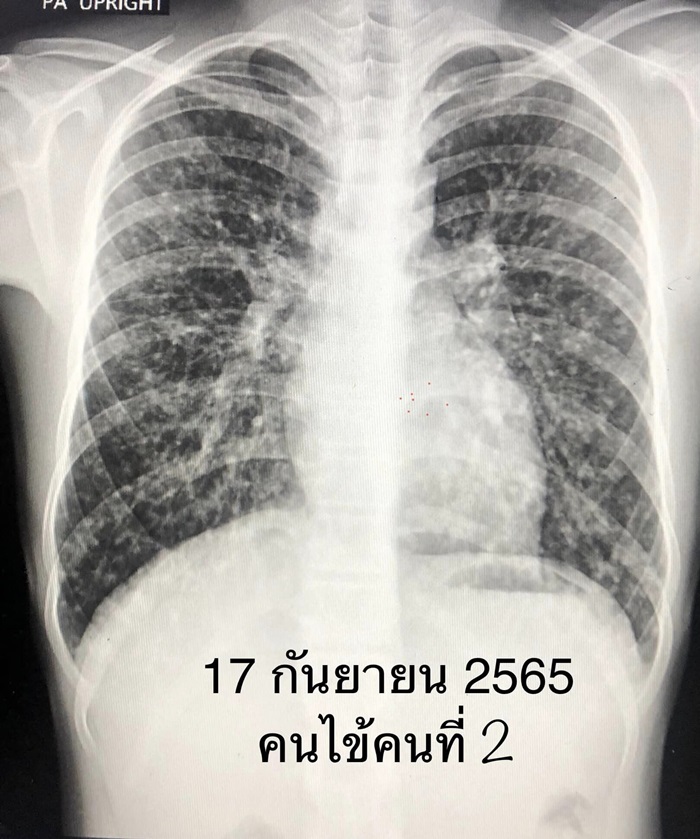

2022년 7월 30일 자연연구회가 나무 구멍에 들어갔습니다. 제가 아는 한, 이 그룹의 10명 중 7명은 나무 구멍에 들어간 지 2~3주 후에 일부 사람들이 아프고 기침하고 피로해지기 시작했습니다. , 그리고 7명의 폐를 엑스레이로 촬영한 결과 폐 전체에 다양한 크기의 반점이 퍼져 있었습니다. 폐에 3mm 크기의 가장 작은 반점이 있는 사람부터 폐 전체에 1cm 크기의 덩어리가 퍼져 있는 사람까지 다양합니다. 폐에 덩어리가 있는 사람은 히스토플라스마증이 있는 것으로 입증되었습니다. 폐에서 생검을 실시한 결과, Histoplasma capsulatum이라는 곰팡이가 폐에서 자라고 분열하고 있는 것으로 나타났습니다.